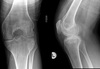

40

22 year old patient. Give 3 differentials in order of likelihood.

1. Infarct 2. Enchondroma 3. Chondrosarcoma

41

43 year old patient. Give 3 differentials in order of likelihood.

1. Chondrosarcoma (>40yrs) 2. Infarct (serpiginous contour) 3. Enchondroma